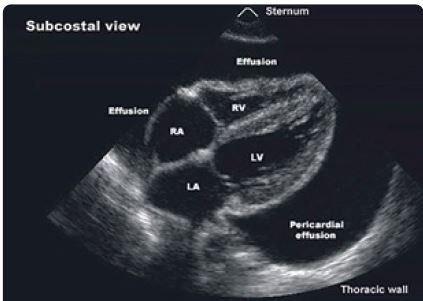

4. Echokardiografie je hlavní zobrazovací metodou v první linii diagnostiky perikarditis. Dokáže kvalitativně a kvantitativně zhodnotit rozsah perikardiální efuze měřením anechogenního prostoru mezi viscerálním a parietálním listem perikardu v enddiastole (výskyt výpotku u 60 % případů). Rozlišujeme malý perikardiální výpotek (< 10 mm), střední (10–20 mm) a velký výpotek (> 20 mm). Ve většině případů nacházíme malý výpotek (80 %), méně často střední (10 %) nebo velký výpotek (10 %), s manifestací srdeční tamponády nebo bez ní (obr. 3, 4). Typickým echokardiografickým nálezem při srdeční tamponádě je obraz „swingujícího srdce“ ve výpotku, kolaps pravostranných srdečních oddílů v diastole, abnormální pohyb komorového septa, zvýrazněná respirační variabilita průtoku mitrální a trikuspidální chlopní > 25 %. V případě myoperikarditis může být systolická funkce komor snížená. V diferenciální diagnóze ischemie myokardu hodnotíme poruchy kinetiky stěn levé komory. Důležité je sledovat dynamiku rozvoje perikardiální efuze, nejen aktuální objem. U pacientů s akutní virovou perikarditis může být echokardiografický nález normální.

Obr. 3 Echokardiografické zobrazení perikarditis s rozsáhlým výpotkem – subkostální pohled.RTG (rentgen) hrudníku bývá u akutní virové perikarditis normální. Může odhalit kalcifikace perikardu, zvětšený srdeční stín, bronchopneumonii, fluidothorax, specifické záněty plic (tuberkulóza, sarkoidóza), nádory plic a mediastina.